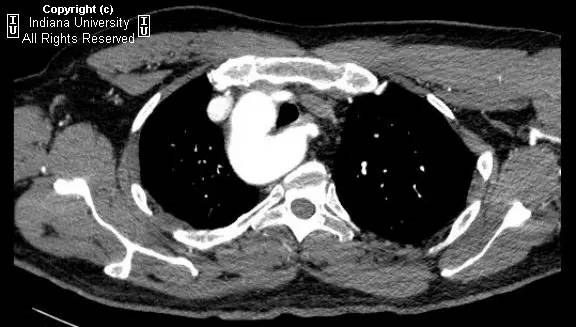

【影像学表现】胸部平片示右位主动脉弓,肺动脉突出,双肺清晰。CT示右位主动脉弓,并右位降主动脉,迷走左锁骨下动脉起自后方,从食管后走形形成血管环。迷走左锁骨下动脉与憩室相关(Kommerell)。食管因左锁骨下动脉及憩室而向前移位。

【诊断】右位主动脉弓并血管环形成、迷走左锁骨下动脉并Kommerell憩室

Right-sided aorticarch, with vascular ring and aberrant left subclavian with Kommerell\’sdiverticulum